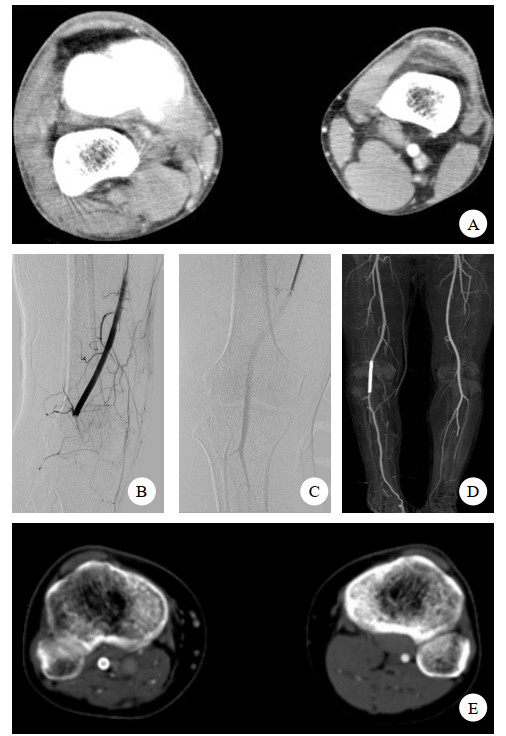

1.3 术后随访术后彩超或CTA,评估腘动脉通畅率及评估腘动脉覆膜支架是否发生变形/断裂。见图 1,图 2。

| 图 2 患者男,42岁 A.左胫骨平台骨折,钝性腘动脉损伤; B. 植入肝素涂层的Viabahn覆膜支架开通腘动脉;C. 术中发现血栓移位栓塞膝下动脉; D. 经导管接触性溶栓1 d后,血栓顺利清除,膝下动脉显影良好 |